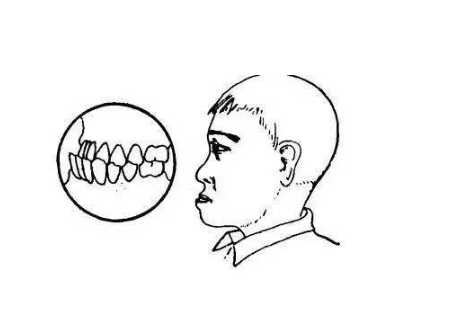

A:俗稱的齙牙是上頜牙齒及上頜骨凸出,會影響咀嚼和發音,還會造成面部不協調不美觀,不同類型的齙牙矯正也不盡相同。對於生長發育期的兒童齙牙,骨骼發育具有很強的可塑性,可通過佩戴活動性矯治器對頜骨進行矯形治療。對於成年人,輕微的齙牙多因單純牙齒前突……

A:齙牙是一種容貌特徵,表現為門牙前突,導致齙牙的原因很多,通常以遺傳因素為主,另外在孩子的牙齒髮育過程中,有可能是因為發育畸形所造成齙牙。出現齙牙的時候,可以通過矯正的方式改善,這種矯正方式,越早會越好,通常有傳統的下顎畸形矯正,這種矯正方式……

A:牙頜畸形分因先天性遺傳因素造成和後天環境因素造成兩種,表現為頷骨、顱面錯位排列不齊形成畸形。建議可先去醫院口腔科拍取牙片,根據牙頜畸形情況制定治療方案,一般,常規的矯正方法有:傳統鋼絲矯正、陶瓷自鎖矯正、舌側隱形矯正和全透明隱形較正等,未成……